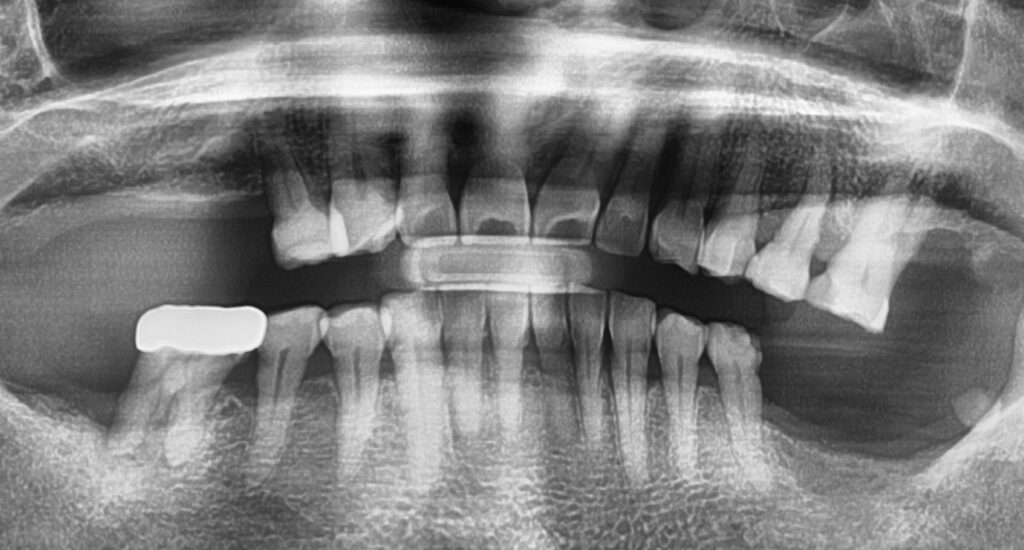

Recently, a 65-year-old patient visited Finesse Dental & Implant Center with multiple missing molars. Her case perfectly illustrates our approach: combining advanced surgical techniques with a conservative clinical philosophy.

The Challenge: Limited Bone and Irregular Sinus Anatomy

Upon initial examination, the patient’s upper right quadrant presented a significant challenge: very limited bone height. In this area, the jawbone was so thin that a standard implant would have lacked the necessary foundation to stay secure.